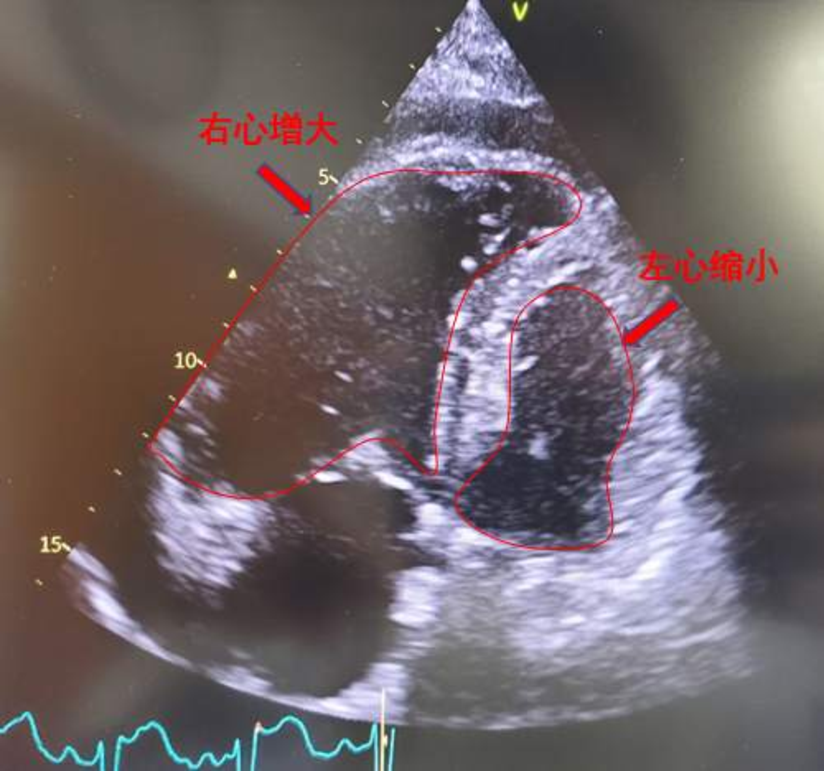

下肢静脉彩超提示双侧小腿多支静脉血管血栓形成。心超彩超示重度肺动脉高压(肺动脉收缩压101mmHg),右心明显增大,TAPSE:1.68cm,少量心包积液(图2)。肺动脉CT(CTPA)示主肺动脉及右肺动脉干明显增宽,右肺动脉干见巨大充盈缺损,叶、段肺动脉均未显影;左侧肺动脉多发分支充盈缺损(图3)。肺动脉造影提示右肺动脉叶段分支均未显影(图4)。

图4 左图为本患者肺动脉造影图,右图为正常肺动脉造影参考图